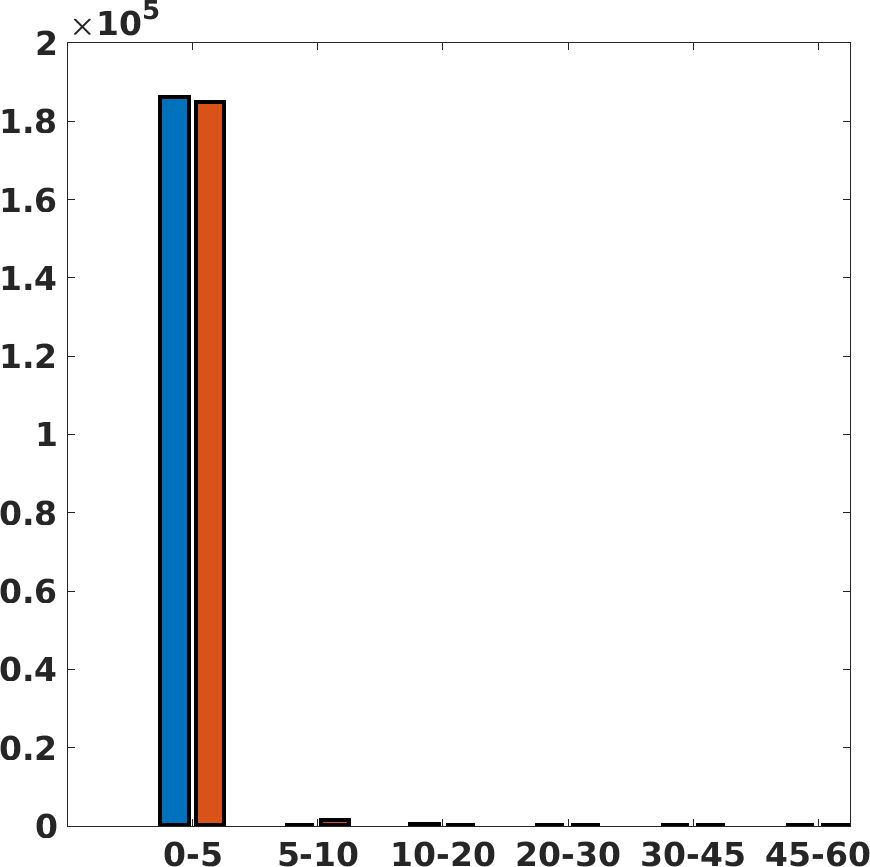

Fig. 7(a-b-c, left) shows the box plot of the statistics of the PSNR on three different anatomical districts, comparing the target images with the prediction and the cubic convolution, respectively. The metrics are computed on a data set of 200 images of the same district and with the same up-sampling factor. We report that the PSNR median value improves of on obstetric 2X raw images, on cardiac 2X raw images, and on abdominal raw 4X images.

Fig. 7(a-b-c, right) shows the histogram of the absolute value of the error with respect to the target image, of the prediction and Cubic convolution results, respectively. The histograms show the number of pixels where the prediction error is lower than 5 (i.e., the first bin of the histogram), which means very similar to the target when visually analysing the images. From the Cubic convolution to the predicted images, this value increases of on obstetric 4X raw images, on cardiac 4X raw images, and on abdominal 4X raw images.

Fig. 17 (left) shows the box plot of the quantitative metrics, comparing the target images with the prediction and the Cubic convolution, respectively. The PSNR metric is computed on a data set of 200 images, belonging to the same district, and with the same up-sampling factor. Analysing the obstetric anatomical district and concerning the corresponding raw images (Fig. 7 (a, left)), the denoising allows the network to significantly improve the results of the up-sampling and the prediction. In particular, comparing the target images with the predicted images, the median PSNR value of obstetric 2X denoised images is 51.8, compared to the median PSNR value of obstetric 2X raw images which is 36.9.